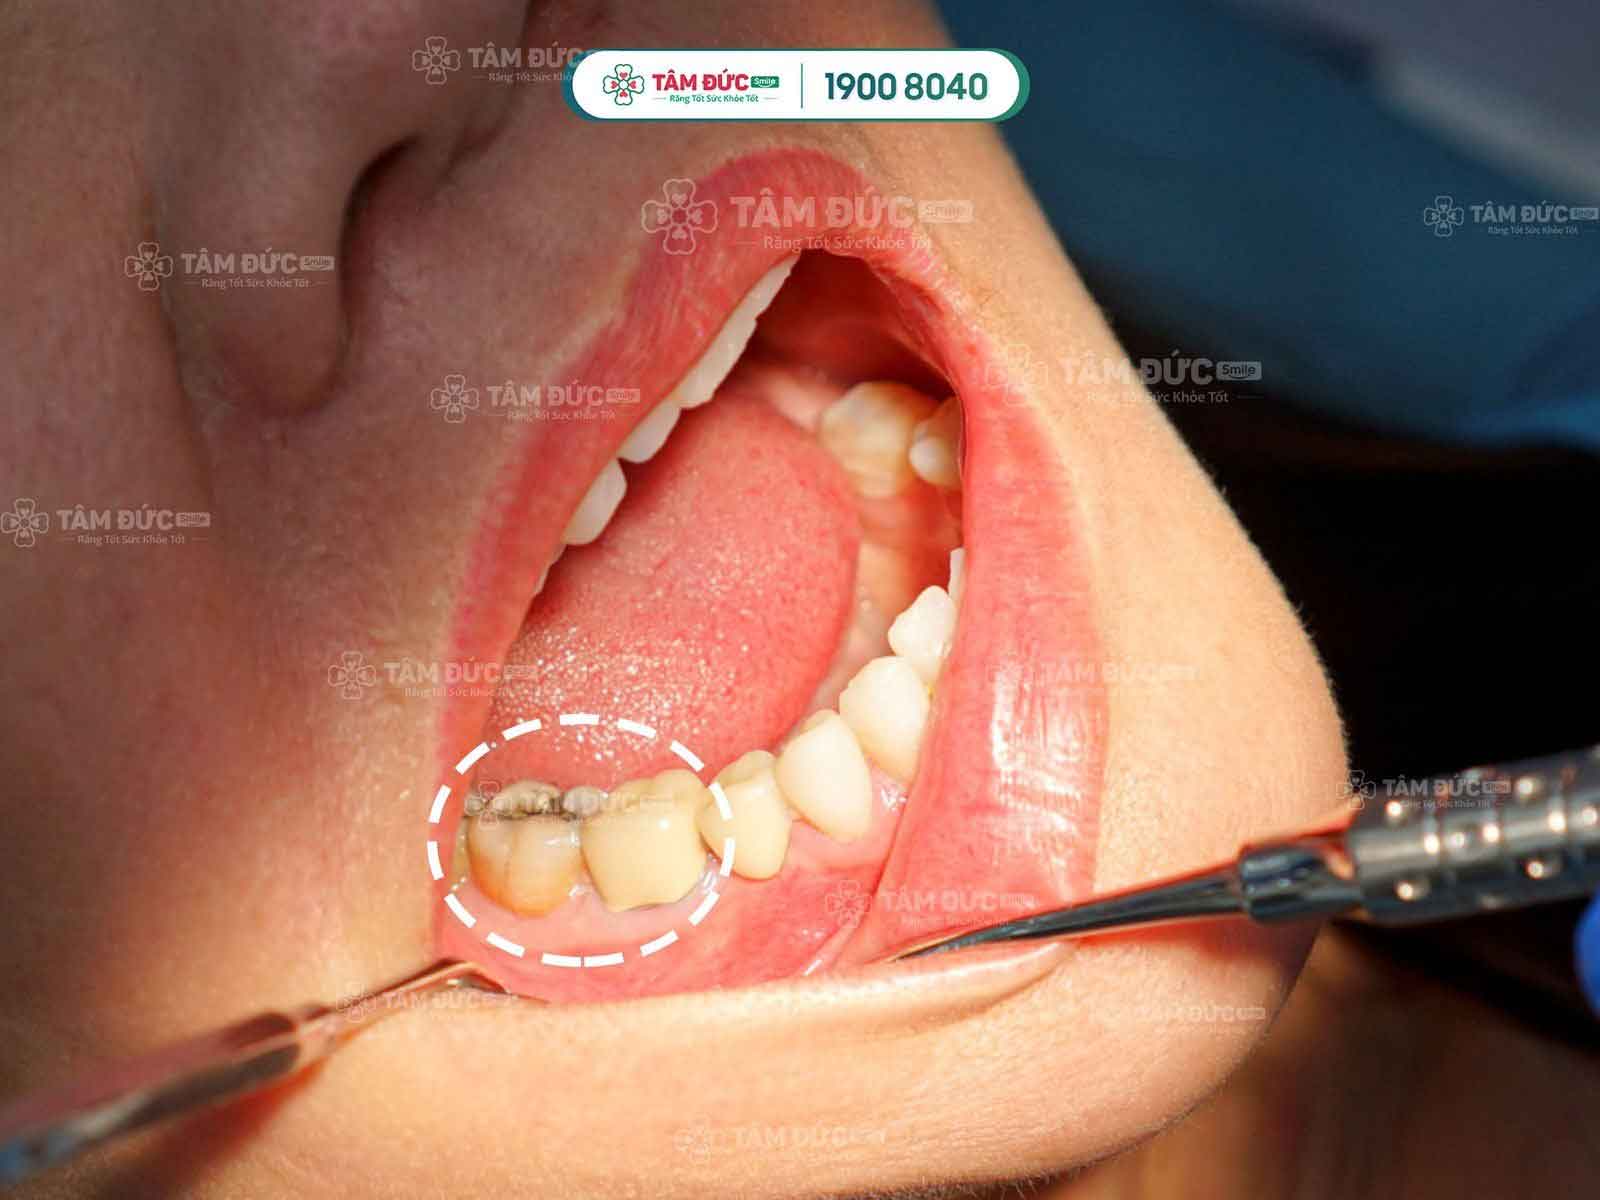

Tuỳ vào tình trạng sâu răng mà bác sĩ chỉ định phương pháp phù hợp

Nếu sâu răng nhẹ: chớm hình thành các lỗ sâu, phương pháp điều trị sâu răng hiệu quả nhất là trám lại lỗ sâu. Bác sĩ sẽ thực hiện làm sạch vết sâu, sau đó sử dụng vật liệu trám răng chuyên dụng để lấp đầy và bít kín các lỗ sâu, ngăn không cho vi khuẩn làm viêm nhiễm sâu vào bên trong tủy răng. Với cách này, vừa giúp điều trị sâu răng, vừa khôi phục lại chức năng ăn nhai một cách nhanh chóng mà tiết kiệm chi phí.

Trường hợp sâu răng nặng: gây viêm tủy, phá hủy mô răng nặng, khi đó tùy vào mức độ viêm nhiễm, bác sĩ sẽ tiến hành điều trị nội nha và trám phục hồi hình dáng răng. Trường hợp xấu nhất, khi các phương pháp điều trị không hiệu quả, sâu răng ăn gần hết răng, hoại tử tủy, viêm nhiễm nặng và có nguy cơ ảnh hưởng tới các răng bên cạnh, khi đó, bác sĩ sẽ chỉ định nhổ bỏ.